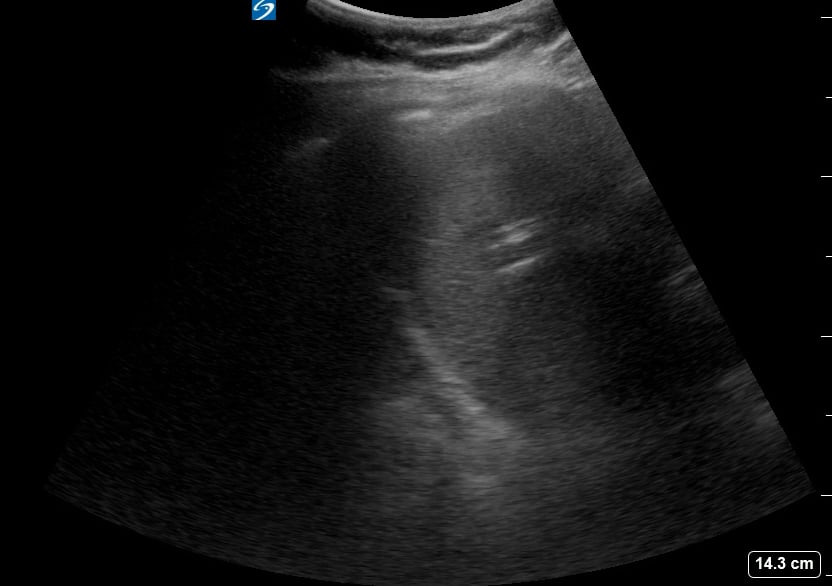

The “curtain sign” in lung ultrasound describes the progressive disappearance of lung tissue from view as the aerated lung expands during inspiration, obscuring deeper structures. This phenomenon resembles a curtain drawing across the screen, indicating normal lung aeration and pleural sliding. It’s a key positive finding, differentiating normal lung from pathologies like pleural effusion or consolidation.

In medical ultrasound, recognizing the curtain sign is vital for accurate diagnosis and patient management. Its presence helps clinicians confirm adequate ventilation in the examined lung region. This acoustic artifact is highly relevant in point-of-care ultrasound (POCUS) to quickly assess lung health and rule out significant pleural or parenchymal abnormalities.